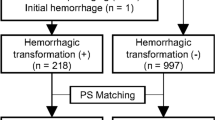

A total of 166 intraparenchymal areas of hyperattenuation from 101 patients were selected for this study (Fig. 2). All the areas of hyperattenuation were randomly assigned to the training cohort (n = 117) and the validation cohort (n = 49). Of the 166 intraparenchymal areas of hyperattenuation, 64 were IPH and 102 were iodinated contrast extravasation. Of the 101 patients, 64 were males and 37 were females. The mean age of the patients was 72.0 ± 11.0 years (range 39–92 years).